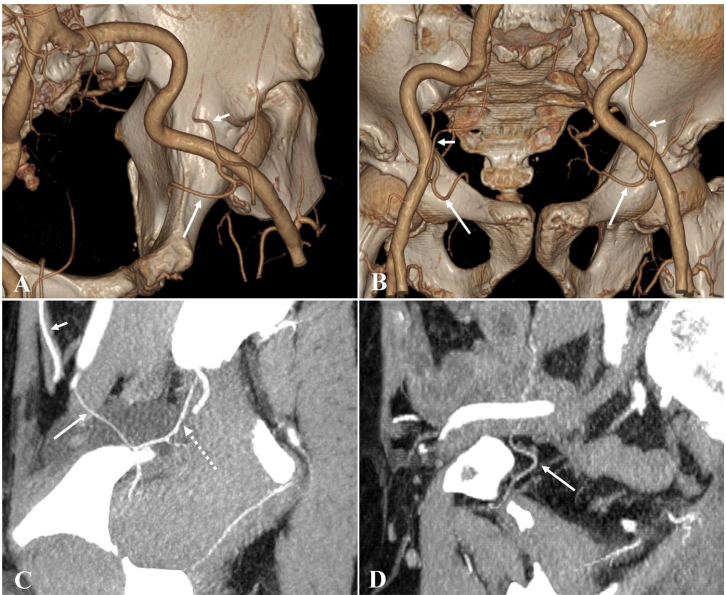

为突破这些局限,张静、黄俊林等研究团队在《Scientific Reports》发表了这项基于CT血管成像的大样本研究。研究人员收集了2018-2024年间719例(1438侧)接受全腹/盆腔CT检查患者的影像数据,采用GE 64排CT进行动脉期和门静脉期双期扫描,通过多平面重建(MPR)、最大密度投影(MIP)和容积再现(VR)等技术,由两位资深放射科医师独立评估CMOR的发病率、血管直径、解剖构型等指标。研究特别建立了标准化的命名体系:异常闭孔动脉(AOA)、异常闭孔静脉(AOV)、血管吻合(VA)等术语均明确定义,并创新性地采用"异常血管+吻合方式+正常血管"的复合命名法。

动脉死亡冠(ACMOR)的发病率与解剖构型

ACMOR检出率为23.92%,按起源和吻合方式可分为四型:I型(92.98%)起源于腹壁下动脉(IEA);II型(5.70%)为(AOA+OA)共干;III型(0.44%)直接起自髂外动脉(EIA);IV型(0.88%)为耻骨支血管。ACMOR距耻骨联合平均距离56.61 mm,女性(62.18 mm)显著大于男性(50.37 mm)。

静脉死亡冠(VCMOR)的发病率与解剖构型

这项研究最突出的贡献在于对VCMOR的系统分类。68.43%患者存在VCMOR,共识别出14种解剖构型,根据髂内外静脉系统间是否存在血管吻合分为两大类型:无血管吻合型(20.75%)包含5种亚型,以单纯AOV最常见(61.45%);存在血管吻合型(79.25%)包含8种亚型,其中AOV+VA+OV构型占比高达81.39%。研究首次发现VCMOR存在三种回流路径:直接汇入髂外静脉(EIV)占主流(756侧),与腹壁下静脉(IEV)共同汇入(83侧),以及单独汇入IEV(16侧)。